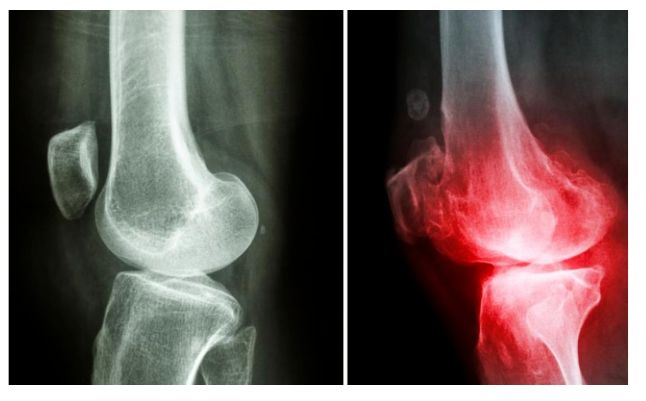

• 阿德莱德大学新发现:骨关节炎有望逆转!

​阿德莱德大学的研究人员发现了一项世界性突破,给饱受瘫痪性骨关节炎折磨的患者带来了新希望。 根据阿德莱德大学的一项新研究,骨关节炎可能是可逆的,该研究将骨关节炎归咎于一种 "gremlin "细胞,而不 ...